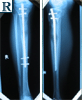

▪ Bilateral tibial

lengthening

▪ Ilizarov with

lengthening-over-nail

technique

▪ Lengthening at 1mm / day

▪ Tibial Intra-medullary nail distal locking

▪ Removal of Ilizarov frame and intra-medullary tibial nailing